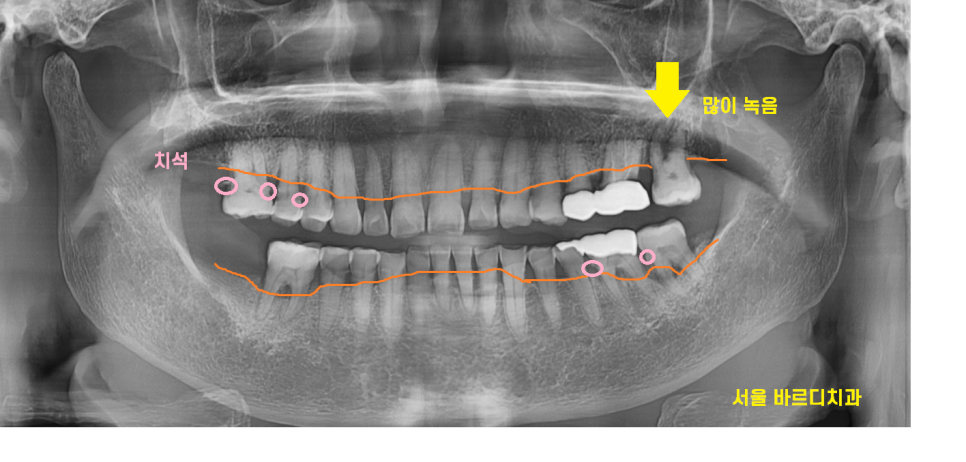

엑스레이상 치석도 보이고..

잇몸뼈도 많이 내려가

풍치가 진행된 상태였는데요.

뼈가 많이 녹은 왼쪽 위에는

뽑아야할꺼같다고 조심스레 말씀드렸습니다.

겉으로는 멀쩡해 보이는데

속은 다.. 녹아서

흔들리고 있었거든요.